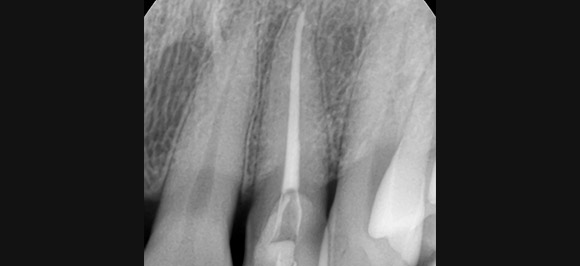

미세현미경을 이용한 신경치료

눈에 보이지 않는 부분까지 세심하고 꼼꼼하게

3~24배 확대로 미세한 공간까지 정밀하고 정교한 치료가 가능